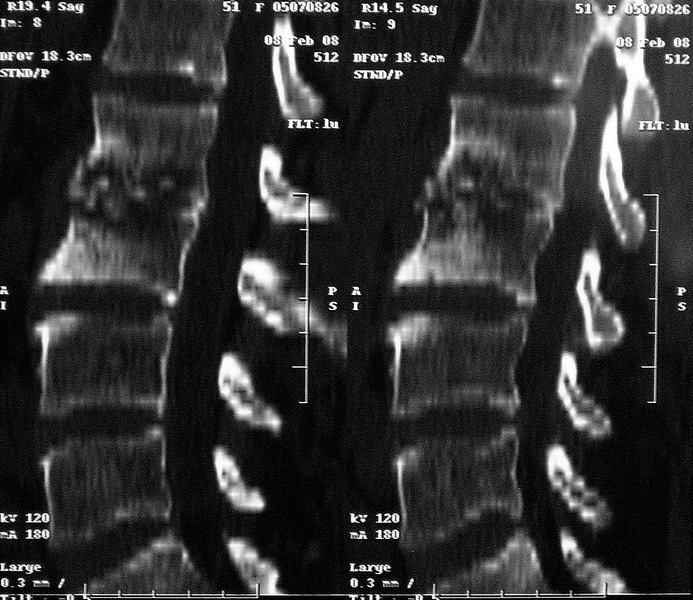

Re: Требуется телеконсультация Вертебролога

послал Коваленко А.Н. 12 Февраль 2008, 22:13

MRI через три недели